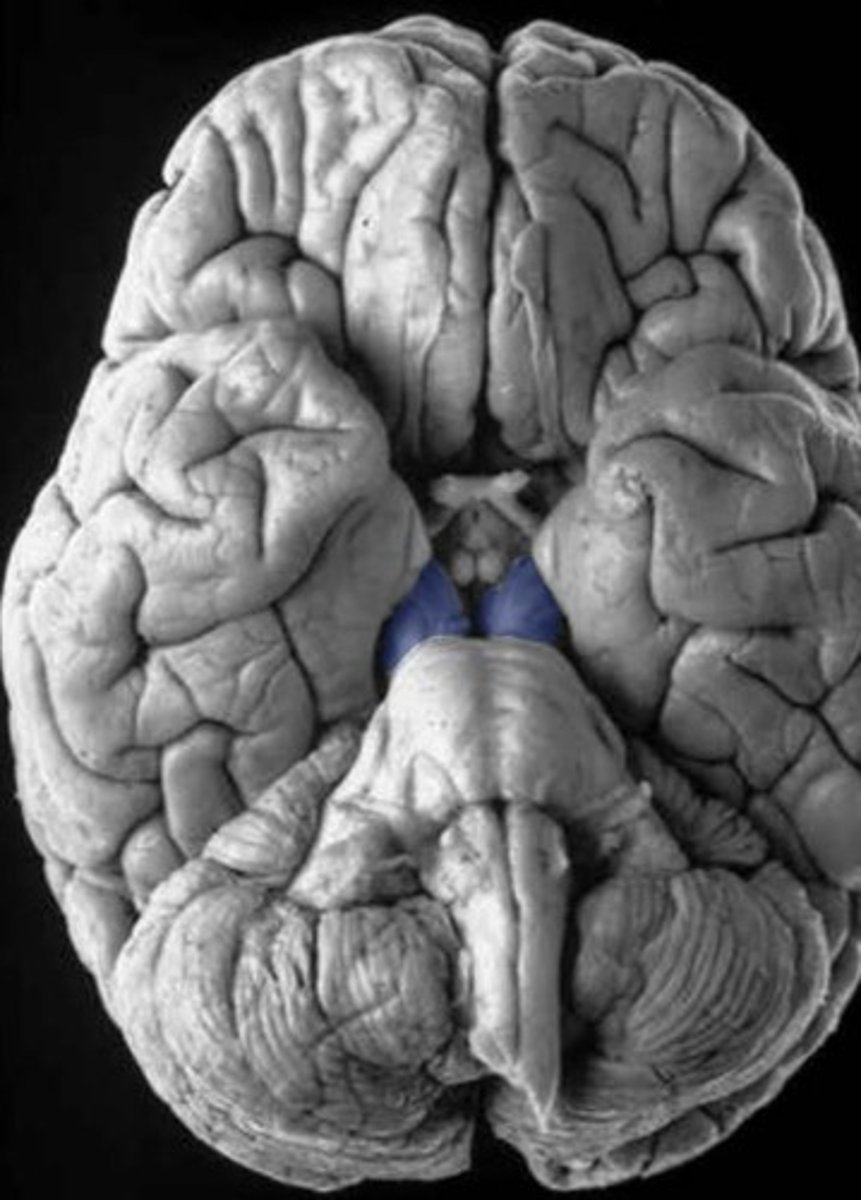

cerebral peduncles, tectum

area separating the cerebral peduncles

interpeduncular fossa

Which cranial nerve emerges from the floor of the interpeduncular fossa?

CN III

refers to the ventral part of the cerebral peduncles

columns of white matter that are the corticospinal and corticonuclear (upper motor neuron fibers going to cranial nerve nuclei) running through the midbrain

basis pedunculi (or crus cerebri)

refers to the dorsal part of the cerebral peduncles

tegmentum

(continuous with tegmentum of pons)